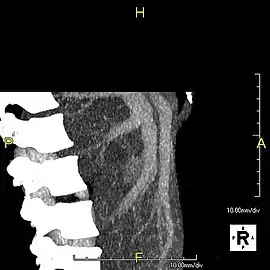

Axial CT image showing anomalous hepatic veins coursing on the liver's subcapsular anterior surface[65]

Maximum intensity projection (MIP) CT image as viewed anteriorly showing the anomalous hepatic veins coursing on the anterior surface of the liver

Lateral MIP view in the same patient as previous image

A CT scan in which the liver and portal vein are shown